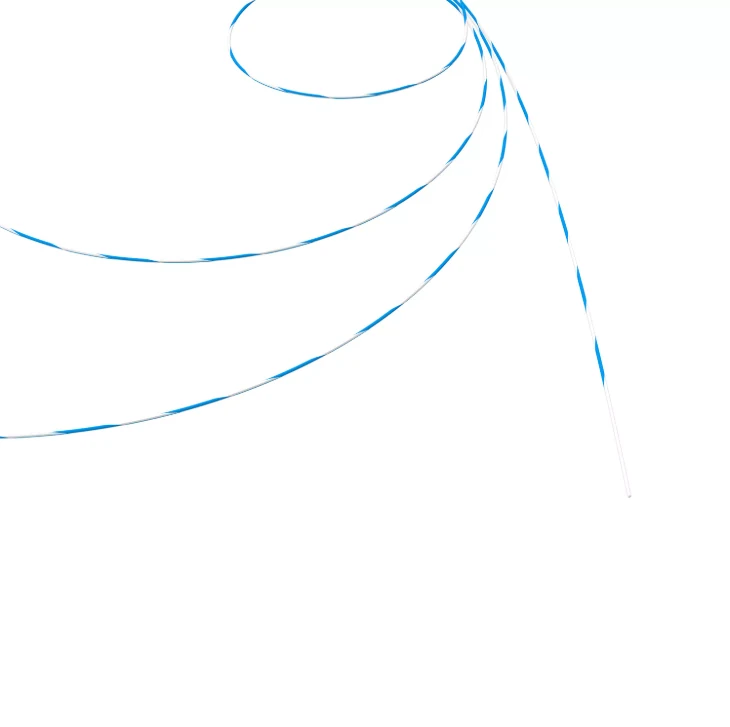

ARIA Wire Rapid Guid – Fio Guia Hidrofílico

Fio Guia Hidrofílico

O fio guia hidrofílico possui revestimento especial que reduz o atrito, proporcionando passagem suave mesmo em trajetos tortuosos ou estreitos. Ideal para acessos difíceis e manipulação atraumática.